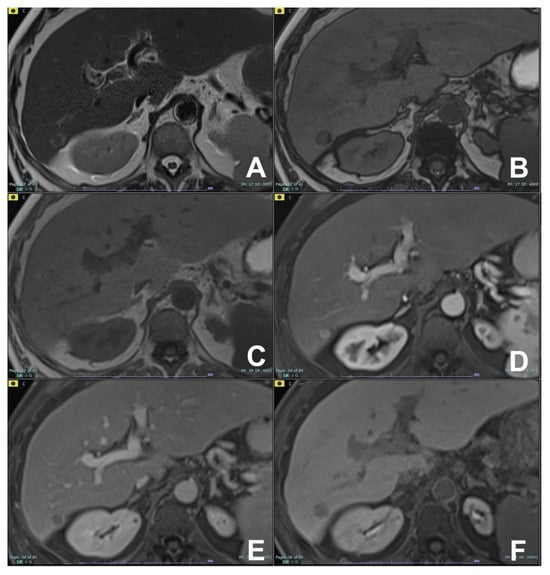

| Cystic lesion of the pancreas (CPL) | HASTE T2 | AXIAL | -- | Anatomy and cysts morphology |

| Indications: MRI is the technique of choice in the diagnosis and management of CPL. T2, MRCP, DWI and contrast enhancement allow one to differentiate the different lesions and suggest an optimal management. As a rule of thumb, benign cystic lesions (serous cystosadenoma) do not require surgical resection or follow-up; border line or malignant lesions (mucinous cystoadenoma; main duct IPMN, BD-IPM with high-risk stigmata) require surgical resection if the patient is fit for surgery, while low-risk cystic lesions (BD-IPMN with no worrisome or high-risk stigmata) require follow-up (see below). | HASTE T2 | CORONAL | -- | Anatomy and cysts morphology |

| GRE T1 FS | AXIAL | -- | Pancreatic parenchima assessment | |

| DWI b 0–50–400–800 | AXIAL | -- | Restricted diffusion inside the CPL can be considered a worrisome feature and injection of contrast is indicated | |

| GRE T1 3D DYNAMIC | AXIAL | Pre- 25″–70″–180″ | Useful for the characterization of worrisome features (thick walls, septa, nodules, restricted diffusion) | |

| MRCP 3D/2D | OBLIQUE CORONAL | Relationship between the wirsung duct and the cystic lesion | ||